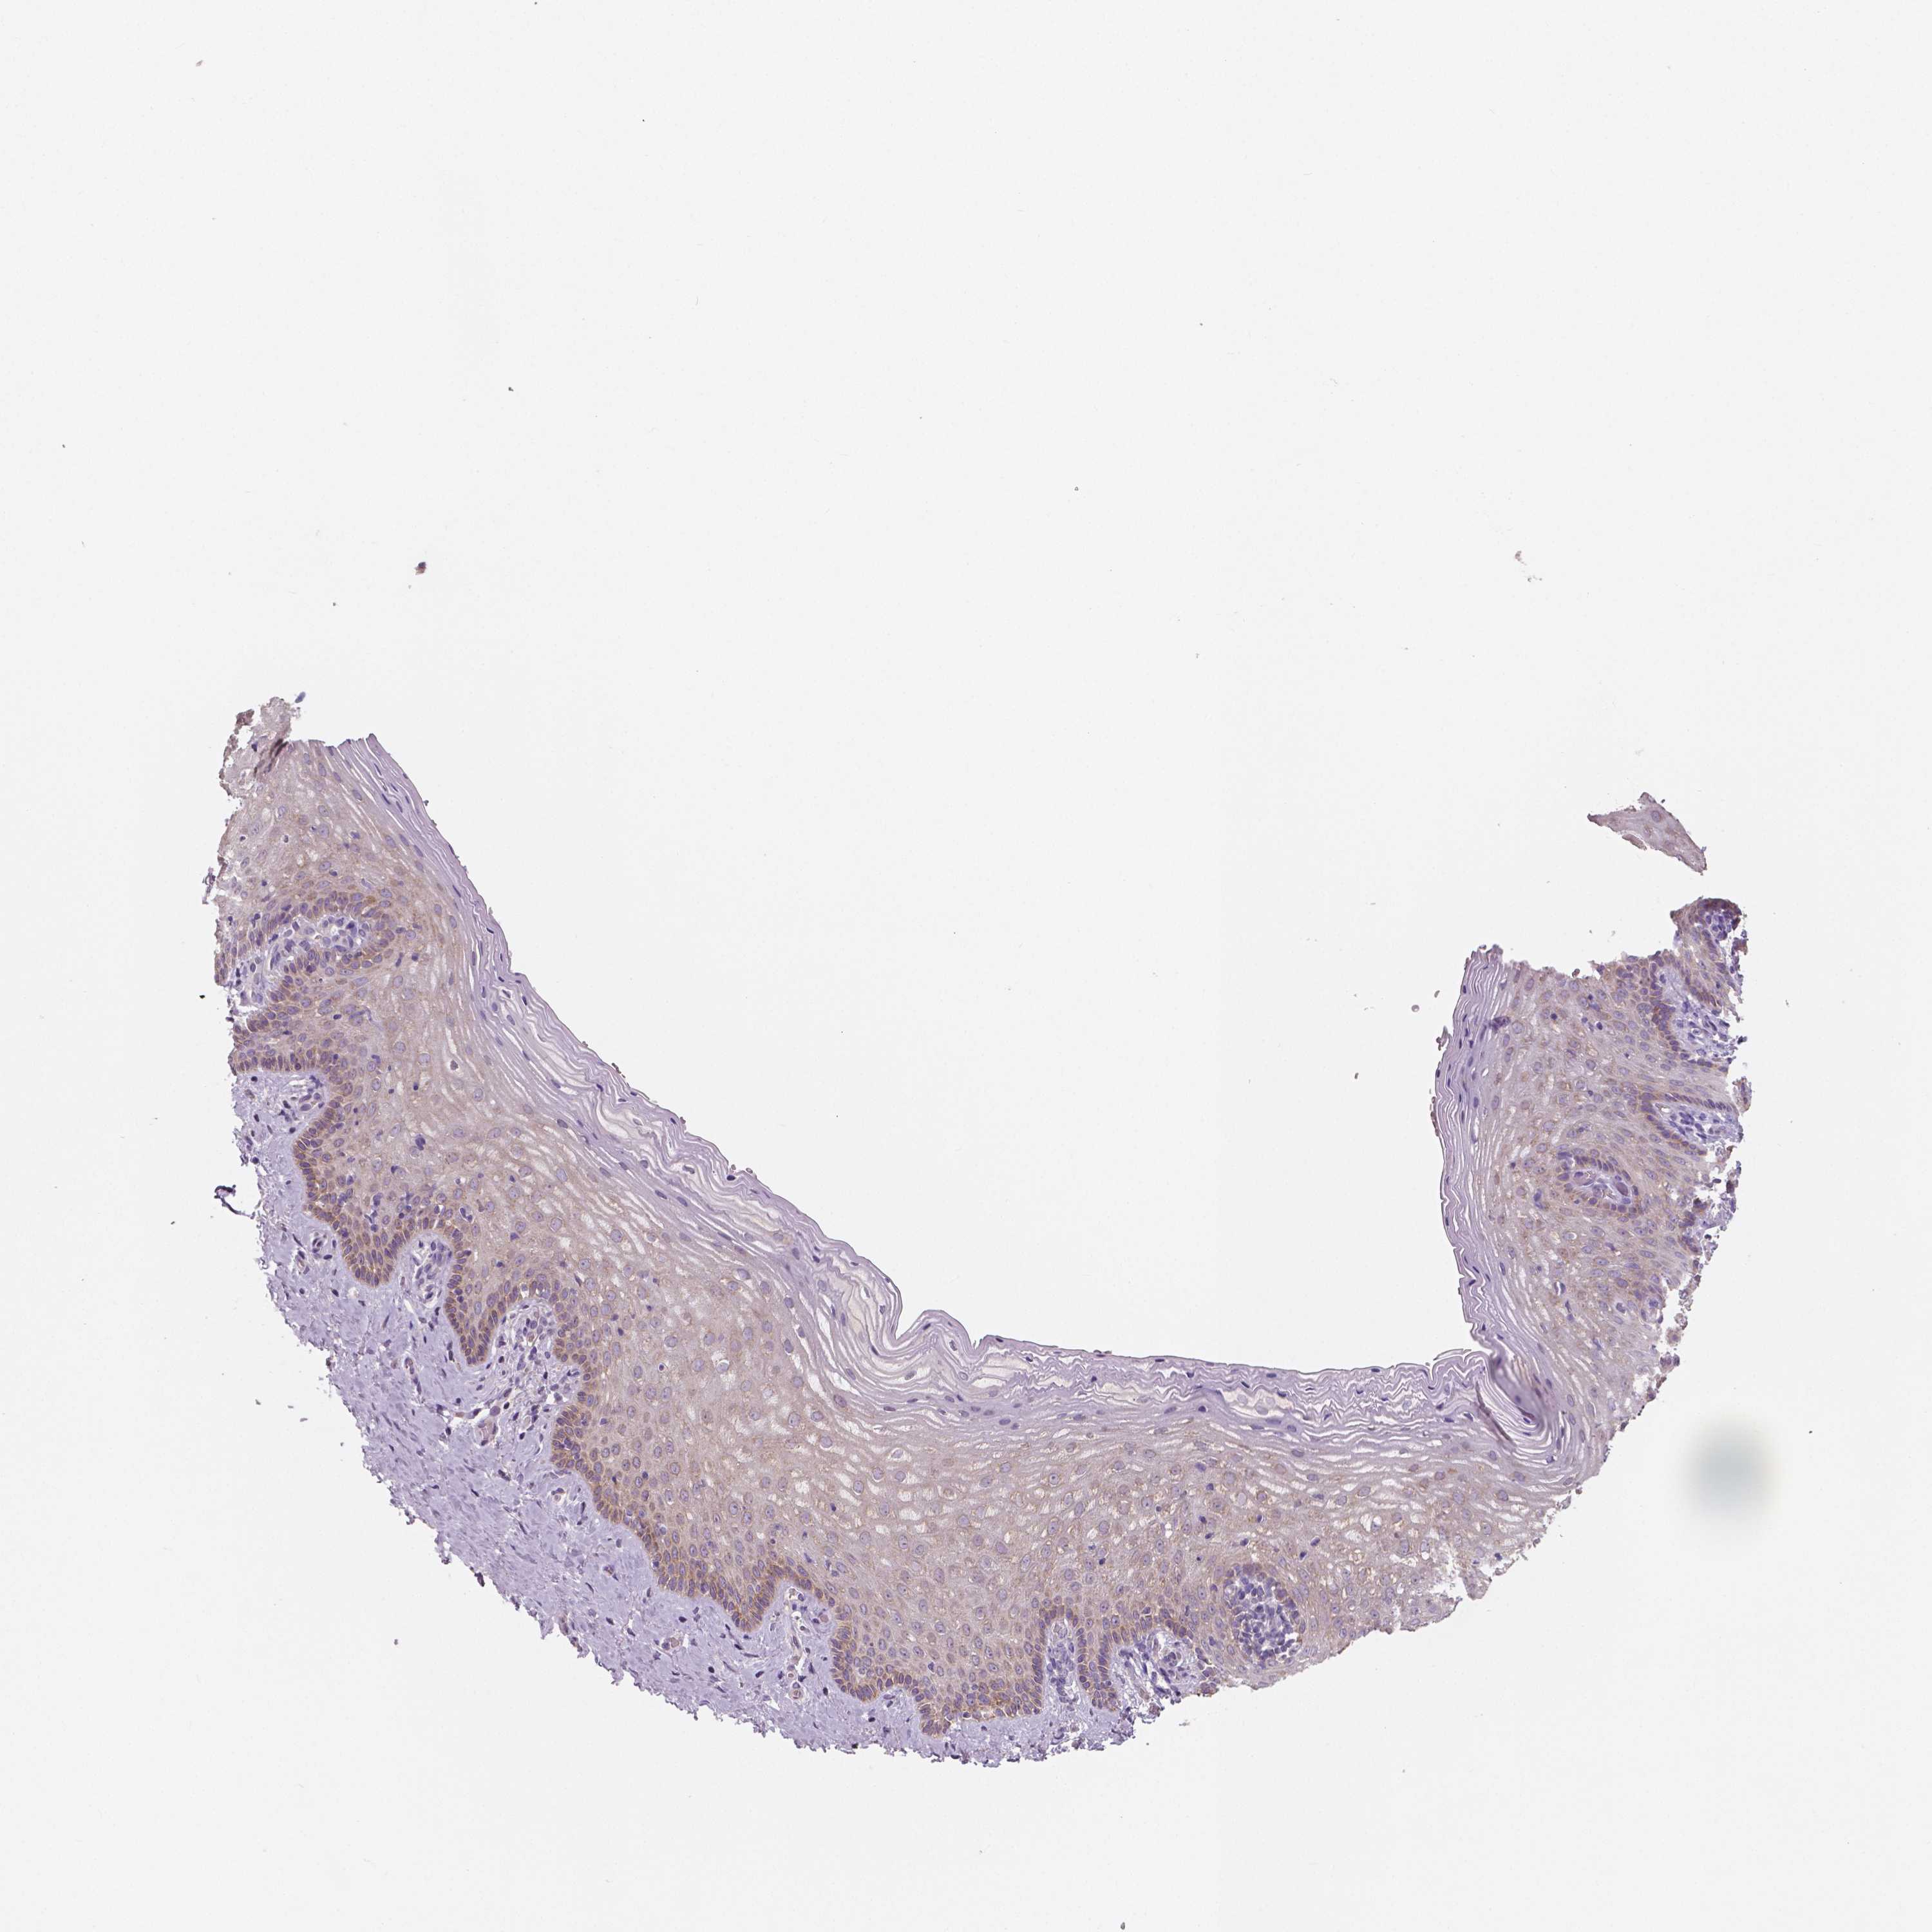

Antibody staining in the annotated cell types in the current human tissue is reported as not detected, low, medium, or high. This score is based on the staining intensity and fraction of stained cells.